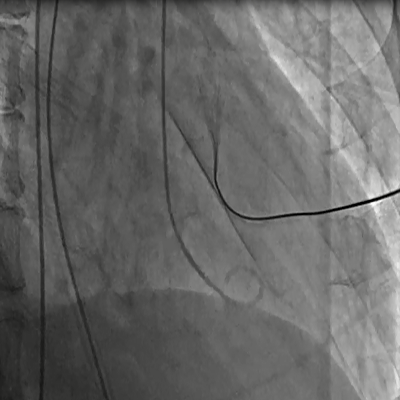

Catheter in the right heart

|

866 KB